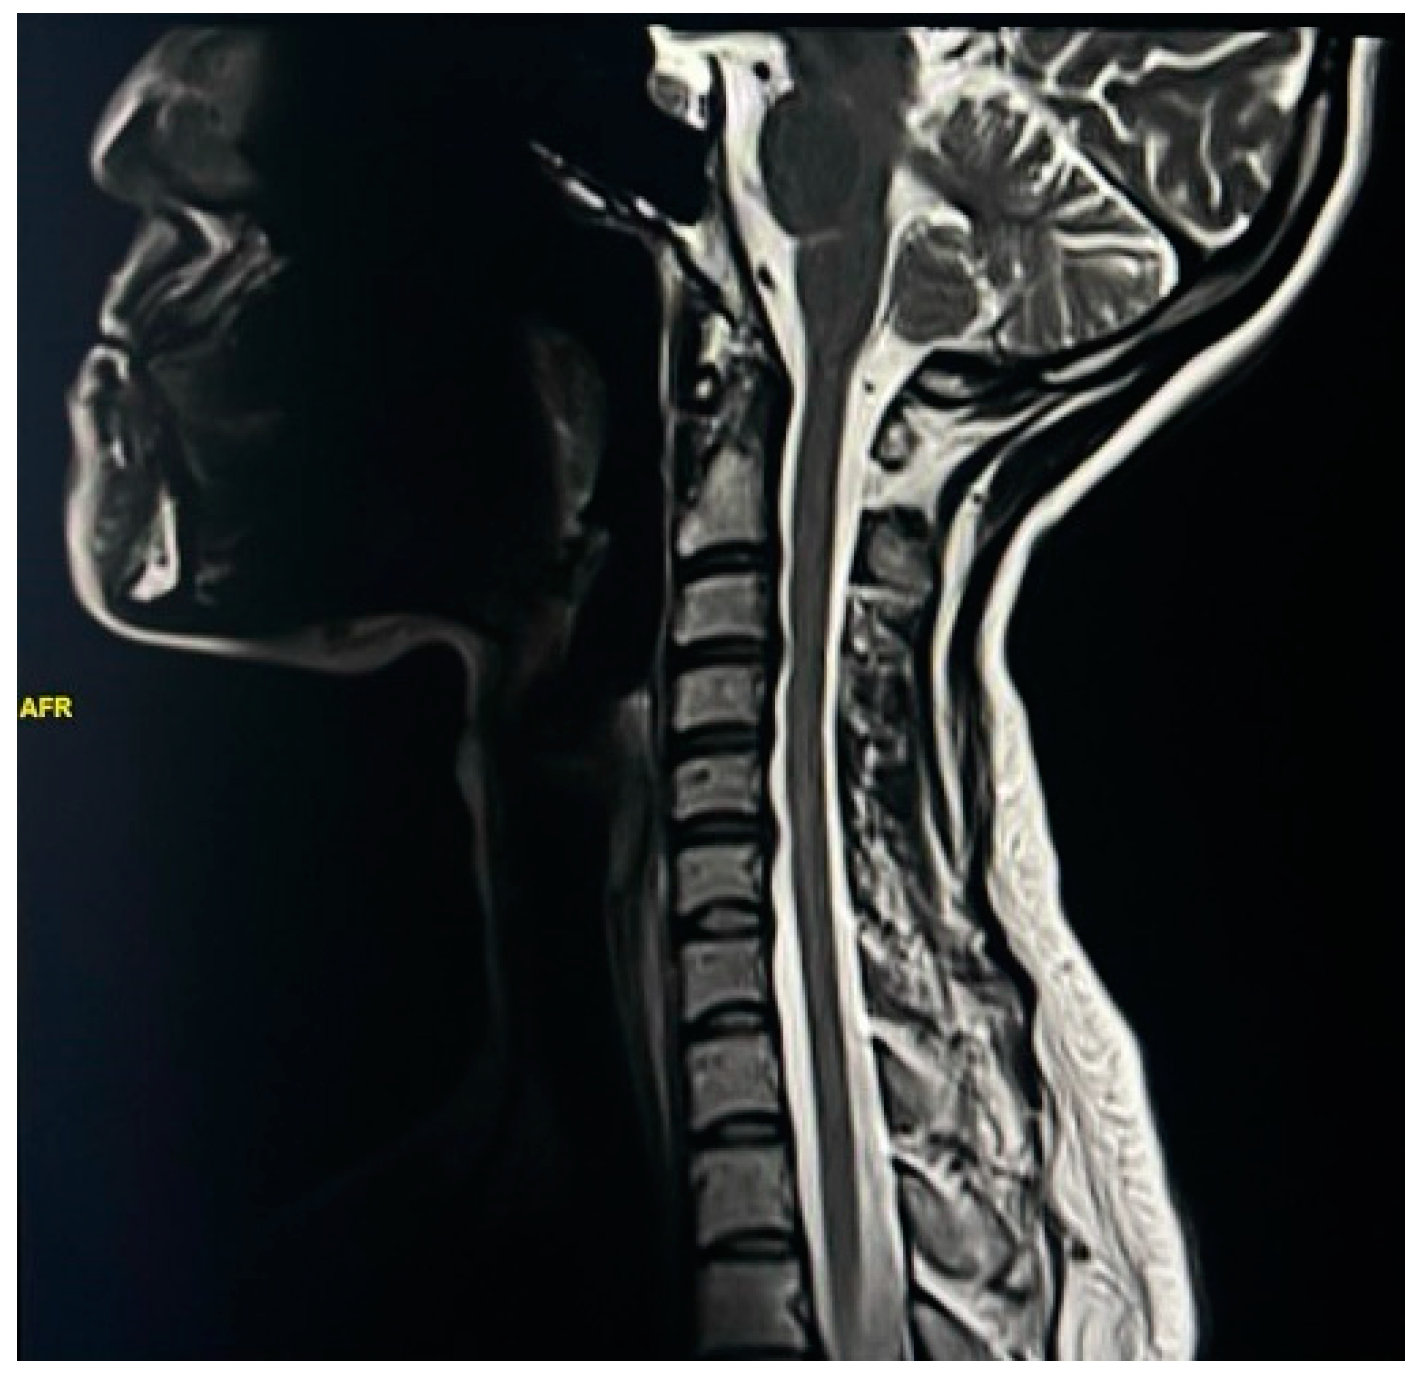

Exploring Spinal Cord Changes in Multiple Sclerosis Patients Using MRI